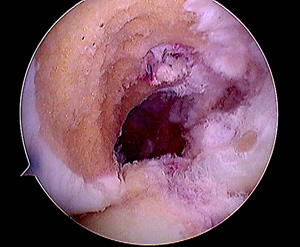

En todos los pacientes de ésta muestra fueron evaluadas radiografías y RMI para determinar las causas de la falla, dividiéndo a los pacientes en 2 grupos en virtud de si las cirugía primaria había sido efectuada por nuestro grupo de trabajo ó por otro. La causa más frecuente de fracaso en nuestra muestra fue el error técnico (75,8%), correspondiendo sólo el 46,8% a un túnel femoral anterior y el 28,5% a un túnel tibial posterior. (Figs.1, 2 y 3)

Figura 1: RX Cross pin protuyendo en artic. Patelofemoral. |

Figura 3: Cross pin protruyendo en articulación patelofemoral por túnel femoral anterior |